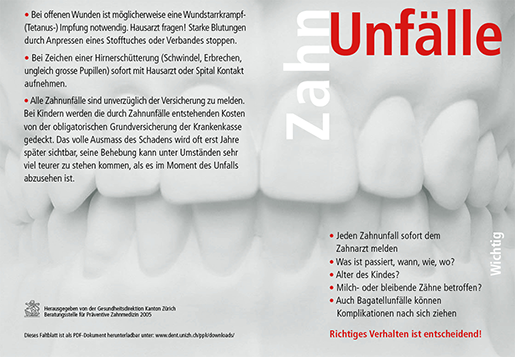

Verhaltensregel

bei einem Zahnunfall

Zahnunfälle geschehen häufiger als man denkt, ob zu Hause, beim Sport oder in der Freizeit. Doch handelt man richtig so lassen sich die meisten Zähne retten.

Bitte bedenken Sie, dass auch Bagatellunfälle Komplikationen verursachen können.

Kontaktieren Sie daher bei Unsicherheiten immer einen Zahnarzt.

Folgende Behandlungen sind innert Stunden nötig!

Beachten Sie unbedingt die nachfolgenden Info-Rubriken.

Zahn ist gelockert

Zahn ist verschoben

Zahn ist hineingeschlagen

Belassen Sie den Zahn in Position und suchen Sie umgehend Ihren Zahnarzt auf.

Behandlung ist dringend. Der Zahn muss eventuell an seinem Platz mit einer Schiene fixiert werden (innert Stunden!).

Zahn ist abgebrochen

Versuchen Sie das abgebrochene Stück zu finden!

Wenn die Möglichkeit gegeben ist, probiert der Zahnarzt dieses wieder anzukleben.

Je mehr abgebrochen, desto dringender ist die Behandlung (innert Stunden!).

Zahn ist herausgeschlagen

Wenn möglich sofort wieder einsetzen!

Sonst sofortiger Transport zum Zahnarzt!

Behandlung innert Stunden nötig!

Zahnunfälle sind versichert. Es ist zu beachten, dass auch Unfälle an Milchzähnen bleibende Schäden an nachwachsenden Zähnen verursachen können. Unfallmeldungen bei Arbeitnehmenden Personen gehen an die Unfallversicherung, bei Nichterwerbstätigen ist die Krankenversicherung zuständig.